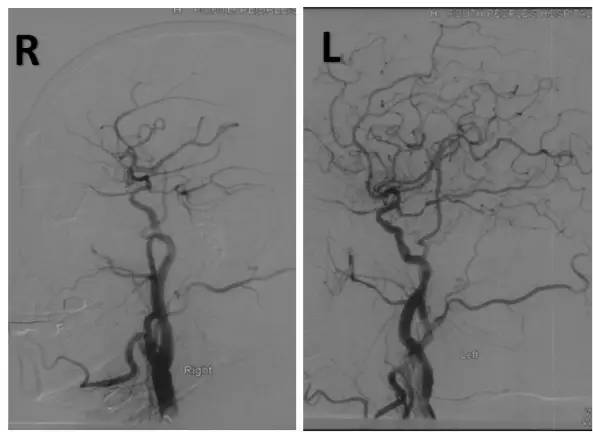

DSA:右侧椎动脉V4段重度狭窄,前向血流减慢,基底动脉近中段未见顺行显影,左侧椎动脉V4段远心端闭塞,右后交通动脉开放,经右颈内动脉造影可见基底动脉中远段显影,左胚胎型大脑后动脉(图3-5)。

图3

图4

图5